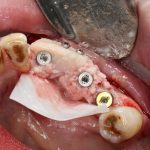

Рекомендации по установке имплантов. Для всех. Часть V.